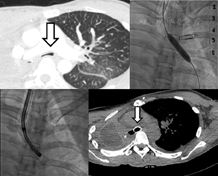

患者 女,50岁。2014年7月因右肺门占位,在全麻下行右全肺切除术。术后病理示:右肺浸润性腺癌(T2aN2N0 ⅢA期)。患者术后恢复情况良好,予"奥沙利铂200 mg d1+培美曲塞二钠800 mg d1"方案化疗2周期,后行胸部放疗1周期(DT50Gy/25fx)。放疗10日后患者出现咳嗽、咳痰,伴有胸闷不适,胸闷、气喘症状持续性加重,遂急来我院就诊。复查胸部CT示右肺术后改变,左肺散在磨玻璃影,左主支气管狭窄(图1)。头颅MR示脑内多发转移瘤,遂行三维TPS治疗。2015年3月9日患者突发昏迷、意识障碍,血压、心率下降,急查动脉血气示:pH 6.96,PaCO2 116.0 mmHg(1 mmHg=0.133 kPa),PaO2 106 mmHg。气管插管后,气管镜下见左主支气管闭塞,气管镜无法通过,吸气时左主支气管稍扩张,呼气时左主支气管塌陷,遂于闭塞处行2次球囊扩张,并在DSA辅助下置入金属支气管支架,气道通畅(图2,图3)。

术后2 h查血气:pH 7.35,PaCO2 41.4 mmHg,PaO2 119 mmHg。术后6 h,患者意识恢复。术后2天,患者生命体征平稳,呼吸困难、胸闷、气喘症状明显缓解,血气分析、血常规、生化等各项指标均恢复正常,复查胸部CT提示左主支气管通畅、支架位置良好(图4)。